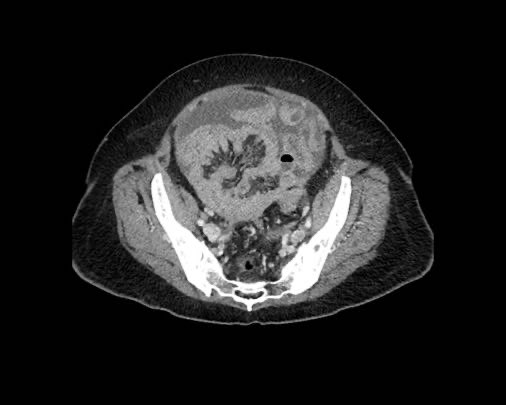

Ở vùng chậu, vị trí quan trọng nhất là túi cùng trực tràng-tử cung và trực tràng-bàng quang (túi cùng Douglas).

Đôi khi có thể thấy di căn khối u lan ra phía trước bàng quang, nhưng không xâm lấn thành bàng quang, do bàng quang là cơ quan nằm ngoài phúc mạc.